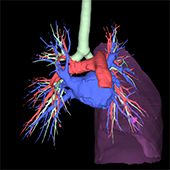

CT検査

CT(Computed Tomography:コンピュータ断層撮影)検査とは、体の周囲からX線を照射することによって断層(輪切り)像が得られる検査です。 CT検査の特徴として、通常のX線撮影などで検出されにくい小さな病変を見つけることができ、広範囲な撮影も可能です。造影剤を用いる事により血管の狭窄や閉塞、瘤の存在や形態を把握できます。また、タイミングを変えて(多時相)撮影することで、腫瘍の良悪性や広がりなどを詳しく調べる事ができます。薄いスライスの画像を重ね合わせて得られる3D(三次元立体)画像は、病変部と血管また骨などの位置関係を多方向から容易に把握できるので、診断や治療等へ活用されています。

当院のCT装置はSOMATOM Force (SIEMENS社製)及び 、Optima CT660 Pro (GE社製)の2台が稼動しており、通常は予約検査で行っておりますが、当日や緊急検査にも対応しています。肺がんを早期発見する為の肺検診では胸部CT検診学会の基準に則った低線量 (X線)で撮影しています。また、心疾患の診断、肺病変の性状を調べる為の肺生検、メタボリックシンドロームの指標となっている内臓脂肪量測定検査なども行っております。

・3D(三次元立体)画像

冠動脈(心臓)

大動脈

下肢動脈